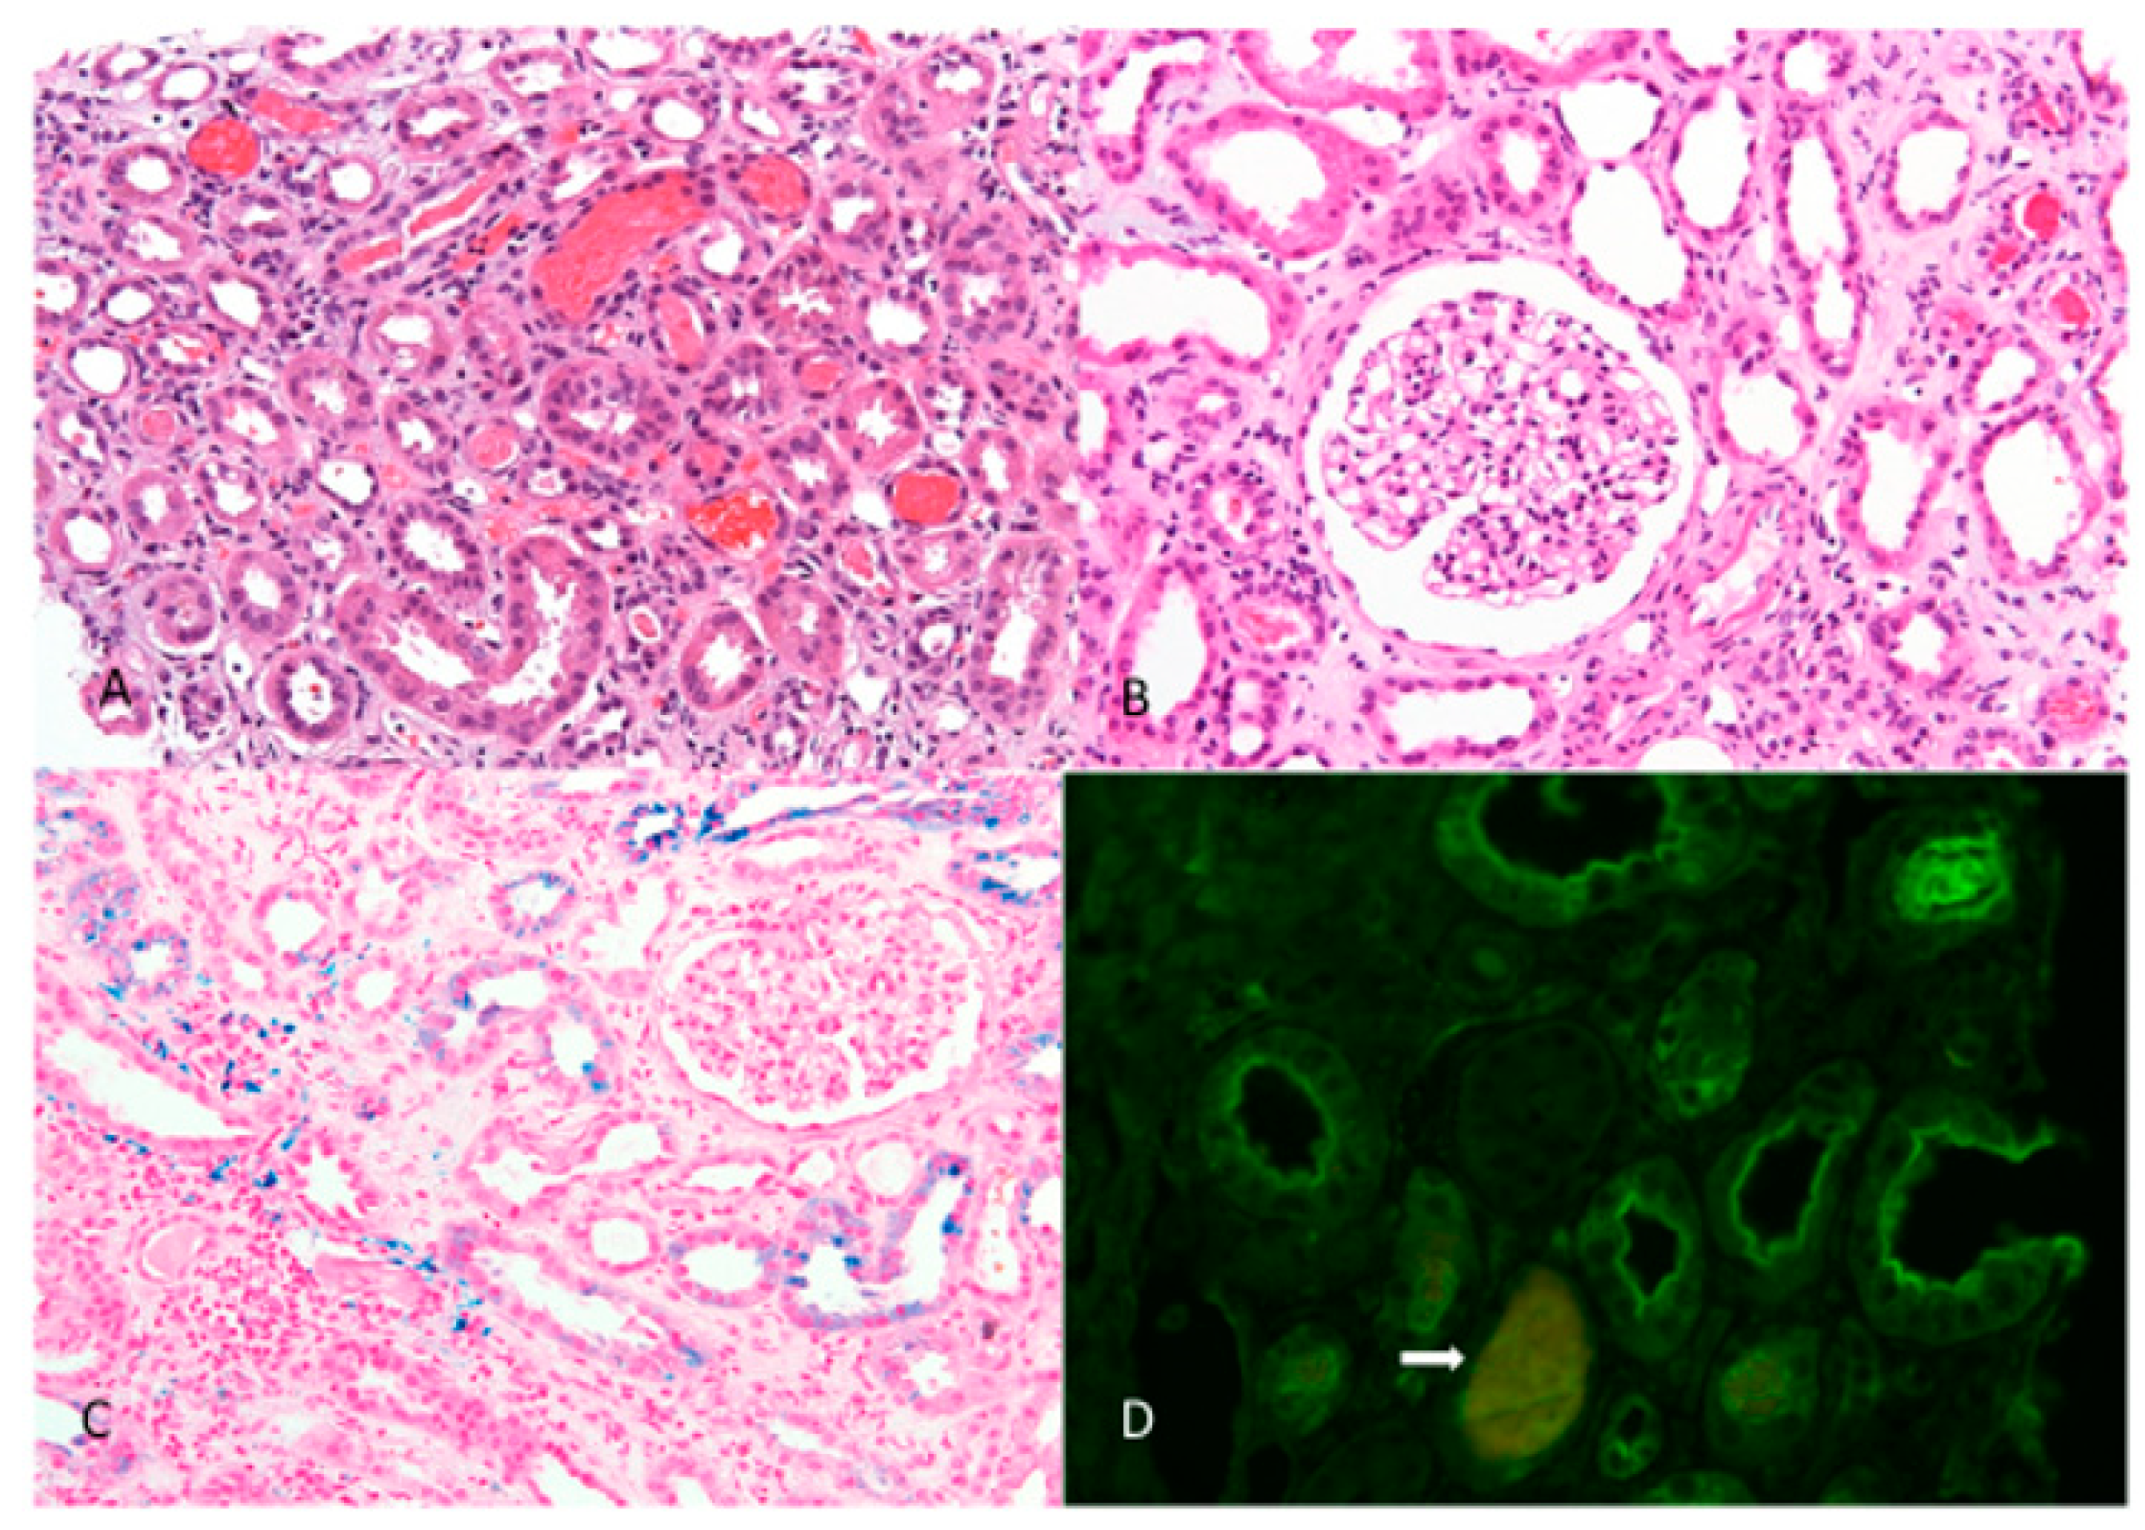

4.2. Histopathological Features

| 9 -case report | ARN, IgAN | M0, E0, S0, T0, C0 | 165–475 nm, average 320 nm | not applicable due to glomerular collapse | 8.10% | 1/11 | 100% | severe | 100% | 5% | tubuli +++ int. ++ | 10% |